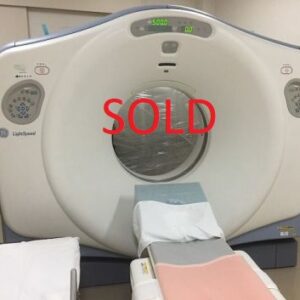

GE LIGHTSPEED RT 16

GE LIGHTSPEED 16

2004 GE LIGHTSPEED 16 SLICE CT SCANNER. Detector channels: 16 x 912. Scan Times:360 degrees, 0.5-0.9 and 1,2,3,4. Slice Thickness mm-0.625, 1.25, 2.5, 3.75, 5, 7.5, 10mm. Gantry Tilt: 30 degrees. X-Ray Tube: 6.3 mHu. X-Ray Generator: 53.2 kW, 10-440 mA’s. Spiral Scanning: yes, Max. scan time: 120 seconds, Max. scan volume: 170 cm. Reconstruction time: 0.1667 seconds. Computer CPU-Open architecture (LINUX). Maximun umber of images displayed at once: 16. Archival Storage: 2.3 GB MOD DICOM 3. CT Angiography: Standard (MiP), and DICOM 3.0 Interface-yes. OPTIONAL: CT Simulation and 3-D Package. This system is available soon. Subject to prior sale.

The used GE Lightspeed RT 16 CT machine is considered one of the world’s leading CT scanners for cancer care. The GE Lightspeed RT 16 CT scanner is a wide-bore system that is easy to operate and features predefined protocols that allow your to perform a wide variety of applications fast and efficiently while delivering exceptional comfort to your patients. This used CT scanner has the power to tackle 3D and 4D imaging as well as display different images simultaneously in real-time..

The refurbished Lightspeed RT 16 is known to be easy-to-use and its ability to display multiple 3D and 4D images simultaneously. The Lightspeed 16 radiotherapy CT is also popular because of its wide-bore opening of 80cm.